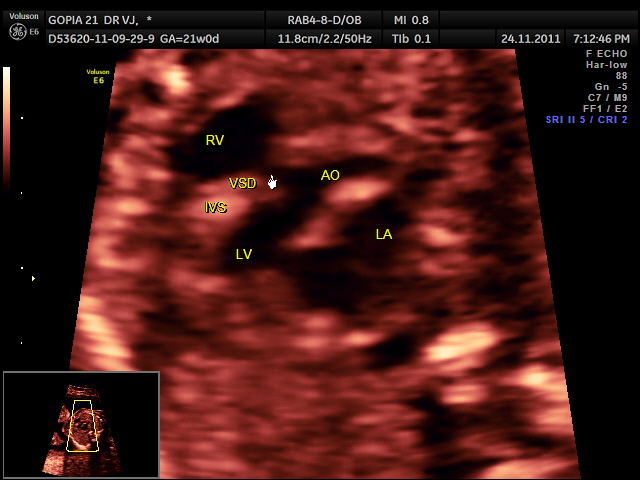

Fetal echocardiography can pick up VSD .

This was a 21 year old primi with h/o consanguinity ; Gestational age at the time of the scan was around 21 weeks .Few of the fetal echo pictures are presented below :

outflow tract VSD is seen